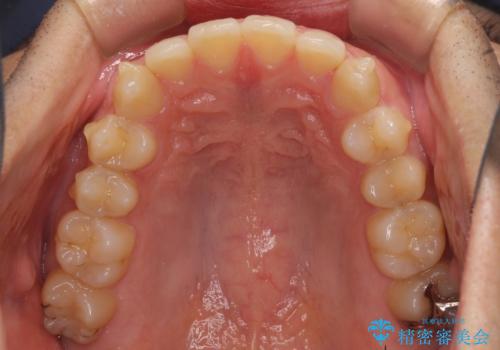

前歯の咬み合わせとデコボコを解消 インビザラインによる矯正治療

- 上下前歯のデコボコと深い咬み合わせを気にして来院された患者様です。

インビザラインによる上下歯列の拡大と、IPR(歯と歯の間を削る)にるスペースの獲得により、前歯のデコボコとディープバイトを改善することとしました。

もう少し下の前歯を整えたかったのですが、患者様の治療を早く終了させたいという希望により、細かい叢生を残しての終了となりました。